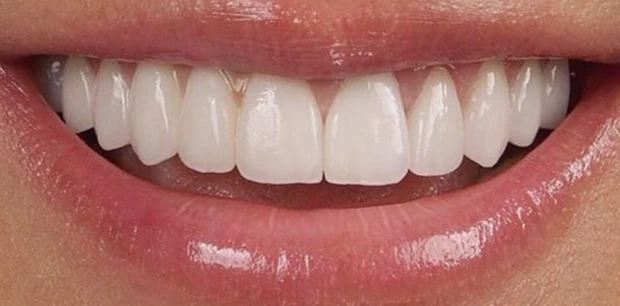

Реставрация, отбеливание

Профессиональное отбеливание зубов

Пациентка Л., 25 лет с жалобами на эстетическую неудовлетворенность цветом зубов. Было предложено провести отбеливание зубов системой ZOOM.